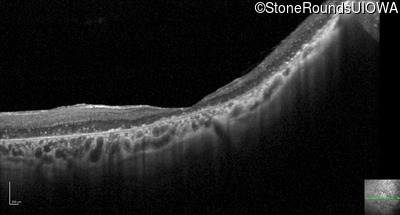

Optical Coherence Tomography - Right - Hand Motion

Exemplar / OCT Stack

OCT Stack